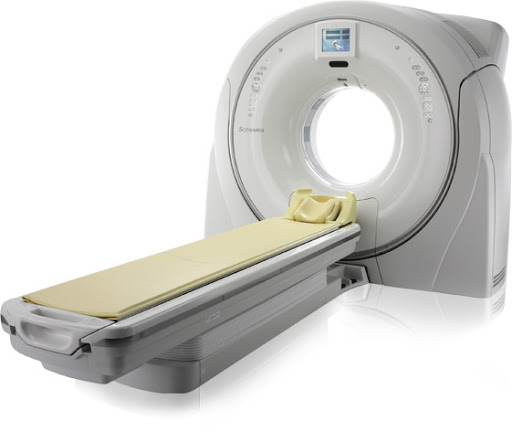

SCENARIA переворачивает традиционное представление о КТ

- Scenaria - это новый компьютерный томограф (64 или 128 среза). Scenaria позволила реализовать все новые возможности, которые способствуют получению высококачественных КТ-изображений.

Открытый дизайн

Достаточно широкая апертура гентри — 750 ммАпертура диаметром свыше стандартных 50 см крайне удобна не только для исследования тучных пациентов, но и для исследования пожилых людей, которым тяжело закидывать руки за голову.

Широкий стол

Широкий стол шириной 475 мм и продуманный специалистами Hitachi до каждой мелочи: матрас с боковыми отворотами позволяют удобно расположить пациента и обернуть его на время исследования. Отвороты матраса также предотвращают попадание капель контраста или крови на движущиеся части стола.